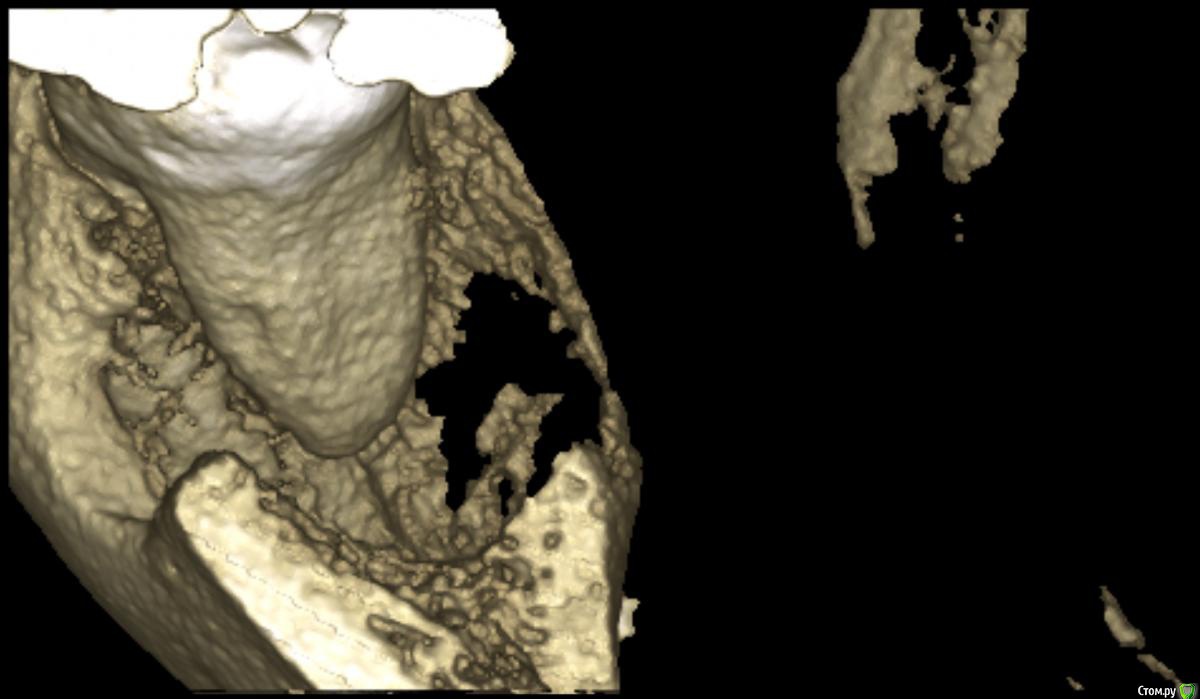

medbratec Опубликовано 12 октября, 2016 Автор Поделиться Опубликовано 12 октября, 2016 Был на консультации в частной клинике.Вердикт - семерку лучше пока не трогать, ее чувствительность обусловлена оголенными корнями. Проводить ревизию лунки, доставать осколок вежливо отказались, и отправляют с этим в челюстно-лицевую.Посоветовали сделать клкт для прояснения картины. Я сделал, однако повторную консультацию пришлось отложить. Не знаю как оттуда вытащить картинки. Если кому будет не лень, то оставлю ссылку на скачивание образа диска. (600мб)Рентгенолог сказал, что осколок в мягких тканях, причем с внутренней стороны, также обнаружилась кариозная полость в месте соприкосновения 7-го и 6-го зуба. Ссылка на комментарий

medbratec Опубликовано 13 октября, 2016 Автор Поделиться Опубликовано 13 октября, 2016 Я вас прекрасно понимаю. Был бы специалистом, то так сразу и сделал. Просто не знаю, что конкретно и под каким углом показывать. Сделал несколько скриншотов. Напишите, если они окажутся не слишком информативны. Ссылка на комментарий

medbratec Опубликовано 13 октября, 2016 Автор Поделиться Опубликовано 13 октября, 2016 Ссылка на комментарий

IvanK Опубликовано 14 октября, 2016 Поделиться Опубликовано 14 октября, 2016 скорее всего , это пломбировочный материал, лежит он не в костной ткани, а в мягких тканях, если не беспокоит, то можно не трогать 1 Ссылка на комментарий

red_butler Опубликовано 17 октября, 2016 Поделиться Опубликовано 17 октября, 2016 если это пломбировочный материал то на снимках "до" он должен быть, но я вижу там что то металлическое 2 Ссылка на комментарий

kramer Опубликовано 22 октября, 2016 Поделиться Опубликовано 22 октября, 2016 если это пломбировочный материал то на снимках "до" он должен быть, но я вижу там что то металлическоеЧисто по снимку похоже на кончик твердосплавного бора. ИМХО. Ссылка на комментарий

Kazankov.Egor Опубликовано 30 октября, 2016 Поделиться Опубликовано 30 октября, 2016 если это пломбировочный материал то на снимках "до" он должен быть, но я вижу там что то металлическоеИли комок йодоформа) Ссылка на комментарий